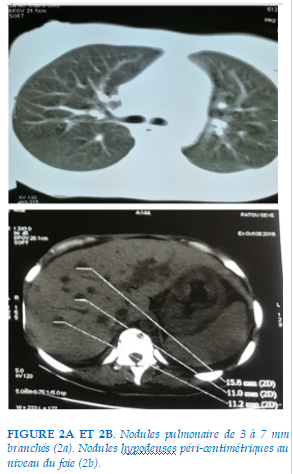

Biologiquement on notait une anémie sévère microcytaire hypochrome (Hb = 7,0g/dl, VGM = 73,7µ3, TCMH = 24,2pg), une thrombopénie sévère (49.000/µl3) sans signes de diathèse hémorragique, une lymphopénie à 186/mm3, une hypocalcémie à 1,55 mmol/l, une hyperphosphorémie à 1,51 mmol/l. Le GeneXpert réalisé dans l’expectoration n’a pas mis en évidence la présence du génome de Mycobacterium tuberculosis. La sérologie rétrovirale était positive au VIH1, le taux des CD4 était à 86/mm3, la charge virale était à 3.413.527 copies/ml. Les sérologies des virus des hépatites B et C étaient négatives. Le scanner thoracoabdominal montrait en fenêtre parenchymateuse, la présence dans le poumon droit de nodules de 3 à 7 mm branchés (Fig. 2a).

En coupes abdominales hautes une douzaine de nodules hypodenses péri-centimétriques au niveau du foie (Fig. 2b) et en fenêtre osseuse des plages d’ostéolyse de 10 à 13 mm de diamètre au niveau des corps vertébraux des 6 vertèbres dorsales (Fig. 2c). La biopsie des nodules cutanés montrait un épiderme d’aspect normal, alors que le derme et l’hypoderme étaient le siège d’une prolifération de petits vaisseaux capillaires parfois monocellulaire, accompagnée d’érythrodiapédèse. Le revêtement endothélial était turgescent. Il s’y associait un infiltrat de cellules fusiformes ou globuleuses organisées en faisceaux ou plages et accompagnées de quelques lymphocytes et plasmocytes. Le traitement antirétroviral à base d’inhibiteur de protéase booster au ritonavir avait été institué associé à une prophylaxie des autres affections opportunistes et à l’acide folinique à la dose de 25 mg/jour. Du fait de la sévérité du tableau clinique une polychimiothérapie à base de l’association Doxorubicine – Bléomycine – Vinblastine avait été décidée. La patiente décède six jours après l’admission dans un tableau de détresse respiratoire aiguë.